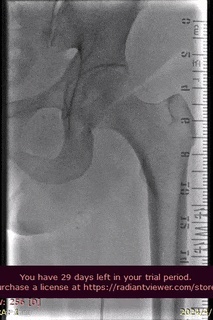

病例分享

山西省人民医院使用分享。

手术过程